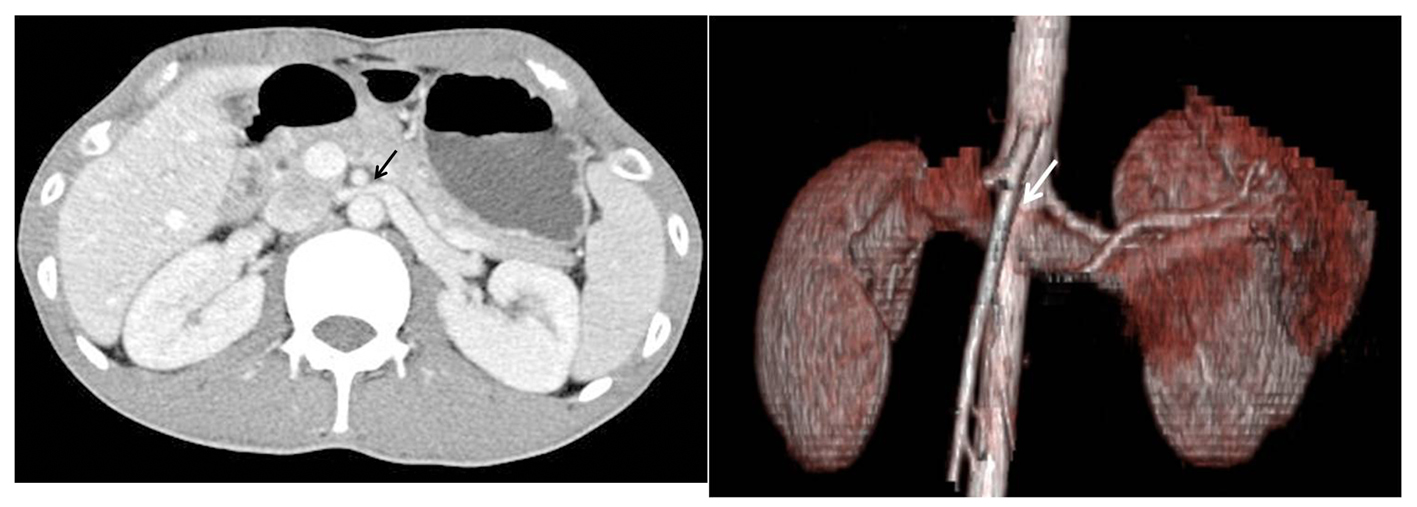

A 26-year-old man visited our institution for evaluation of proteinuria. He intermittently presented with acute urinary retention. Other urological evaluations were unremarkable. Urinalysis exhibited trace proteins without hematuria. Renal duplex and enhanced computed tomography (CT) of the abdomen and pelvis were performed. The duplex ultrasound typically demonstrated aortomesenteric anatomy with entrapment of the left renal vein (LRV) (Fig. 1). The diameters of the LRV at the hilar and aortomesenteric portions were measaured as 11 mm and 1.2 mm, respectively. The duplex ultrasound also indicated a significantly higher ratio of the peak systolic velocity (PSV) to the hilar renal vein PSV at the point of renal vein compression (> 6). This observation demonstrates the diminished volume of flow and dampened pulsatility upon spectral analysis of the left renal vein. Enhanced CT angiography revealed compression of the left renal vein between the aorta and the superior mesenteric artery (Fig. 2). The Nutcracker syndrome is defined as a rare cause of hematuria and flank pain caused by compression of the left renal vein between the aorta and the superior mesenteric artery where it passes at the point of bifurcation of the arteries [1]. The observed compression causes venous hypertension and the formation of renal venous collaterals leading to the subsequent rupture of the septum between the veins and the collecting system, and finally, resulting in hematuria and flank pain [2, 3]. In this particular patient case, although rare, the nutcracker should be included as the potential cause of proteinuria in addition to hematuria in the absence of other renal diseases.

![]() Click for large image | Figure 2. Enhanced CT angiography revealed compression of the left renal vein between the aorta and the superior mesenteric artery. |